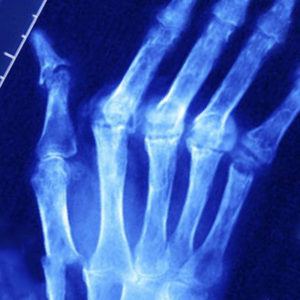

Диагностика псориатического артрита во многом основана на наличии ряда характерных рентгенологических признаков заболевания:

Помимо рентгенографии пациентам с подозрением на псориатический артрит назначают: